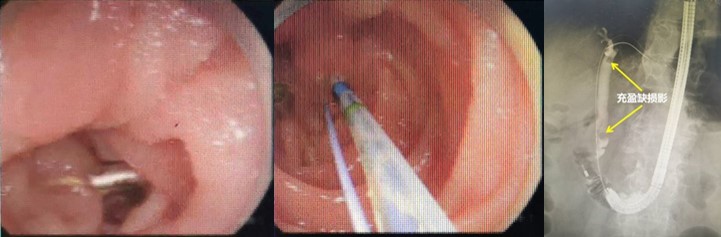

面对如此紧急的情况,干部保健病区冯建军主任联合消化内科赵刚副主任迅速启动了绿色通道,为刘爷爷进行了初步的稳定治疗,同时召集多学科专家进行紧急会诊。专家们一致决定先进行胃镜检查,了解患者既往手术方式,同时为可能的ERCP操作进行“探路”。后经胃镜检查,明确老人确实为“毕Ⅱ式远端胃部分切除”术后改变,内镜下反复寻找后,终于找到输入袢肠管以及十二指肠主乳头,同时为了后续手术时便于再次寻找,以一枚金属夹在十二指肠主乳头旁侧进行标记。

赵刚副主任第一时间也将情况汇报给了李路主任,李主任表示在确保患者安全的基础上科室全力支持并配合此次手术。经再次与患者家属沟通病情并获得充分的知情同意后,ERCP胆管取石术立即展开。

赵刚副主任凭借丰富的经验和精湛的技术,运用胃镜佩戴透明帽顺利找到前期设定的钛夹标记及十二指肠主乳头,然后利用专业器械,在内镜精细操作下,成功进行乳头括约肌切开及球囊扩张术,并最终将胆管内结石顺利取出。整个操作用时不到20分钟。